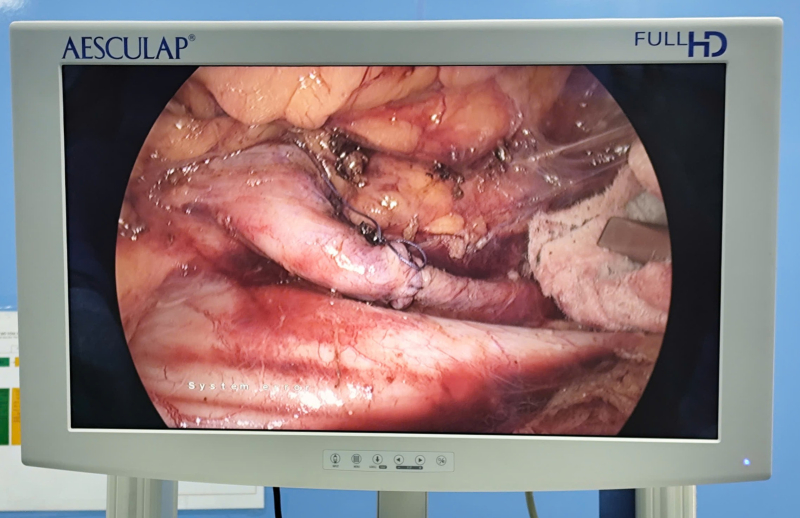

BSCKII Dương Xuân Hiệp cùng êkíp đang tiến hành phẫu thuật cho bệnh nhân.

Hình ảnh: Niệu quản phải được phẫu thuật chuyển vị ra trước tĩnh mạch chủ dưới.

Sau

khi hội chẩn chuyên môn, các bác sĩ chỉ định phẫu thuật nội soi ổ bụng chuyển vị niệu quản ra trước tĩnh mạch chủ dưới.

Quá trình phẫu thuật được thực hiện tỉ mỉ, khéo léo nhằm bóc tách an toàn hiệu quản, tránh tổn thương tĩnh mạch chủ và các cấu trúc lân cận. Đồng thời tiến

hành tán sỏi niệu quản trái, đặt sonde JJ 2 bên.

Sau gần 2 giờ, Kíp phẫu thuật do BSCKII Dương Xuân Hiệp, Trưởng khoa Ngoại tổng hợp, phụ trách phòng TCCB cùng ê kíp đã phẫu thuật thành công, niệu quản được tái tạo lưu thông tốt, chức năng thận được bảo tồn tối đa. Sau mổ, bệnh nhân hồi phục tốt, tiểu tiện bình thường.